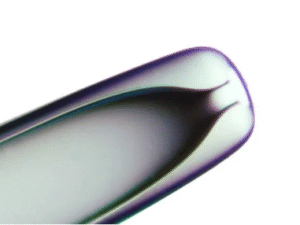

This diverse range includes micropipettes designed to be suitable for all routine micromanipulation techniques:

ICSI – The direct load and injection of a single sperm into an oocyte to facilitate fertilization

Biopsy – Polar body or cell sampling from an embryo for genetic testing

Holding – Stabilizes or manipulates oocytes or embryos

Zona dissection – Removes or “thins” the outer layer (zona pellucida) of the embryo

Assisted hatching – Creates an opening in the zona pellucida

Each micropipette is designed to be compatible with standard microscope systems used in fertility laboratories, allowing for seamless integration into existing workflows.